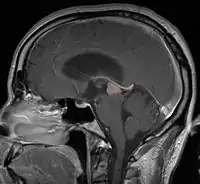

Pineal Gland Tumors

Clinical Presentation

- Determined by the spatial anatomy and direction of growth

- Obstruction of aquaduct: hydrocephalus presenting as headaches, nausea, vomiting

- Compromise of superior colliculus: vertical gaze palsy, pupillary and oculomotor nerve paresis (Parinaud syndrome)

- Progressive growth: cranial nerve neuropathies, hypothalamic dysfunction

- Work-up includes MRI, CSF, serum markers for bHCG and AFP